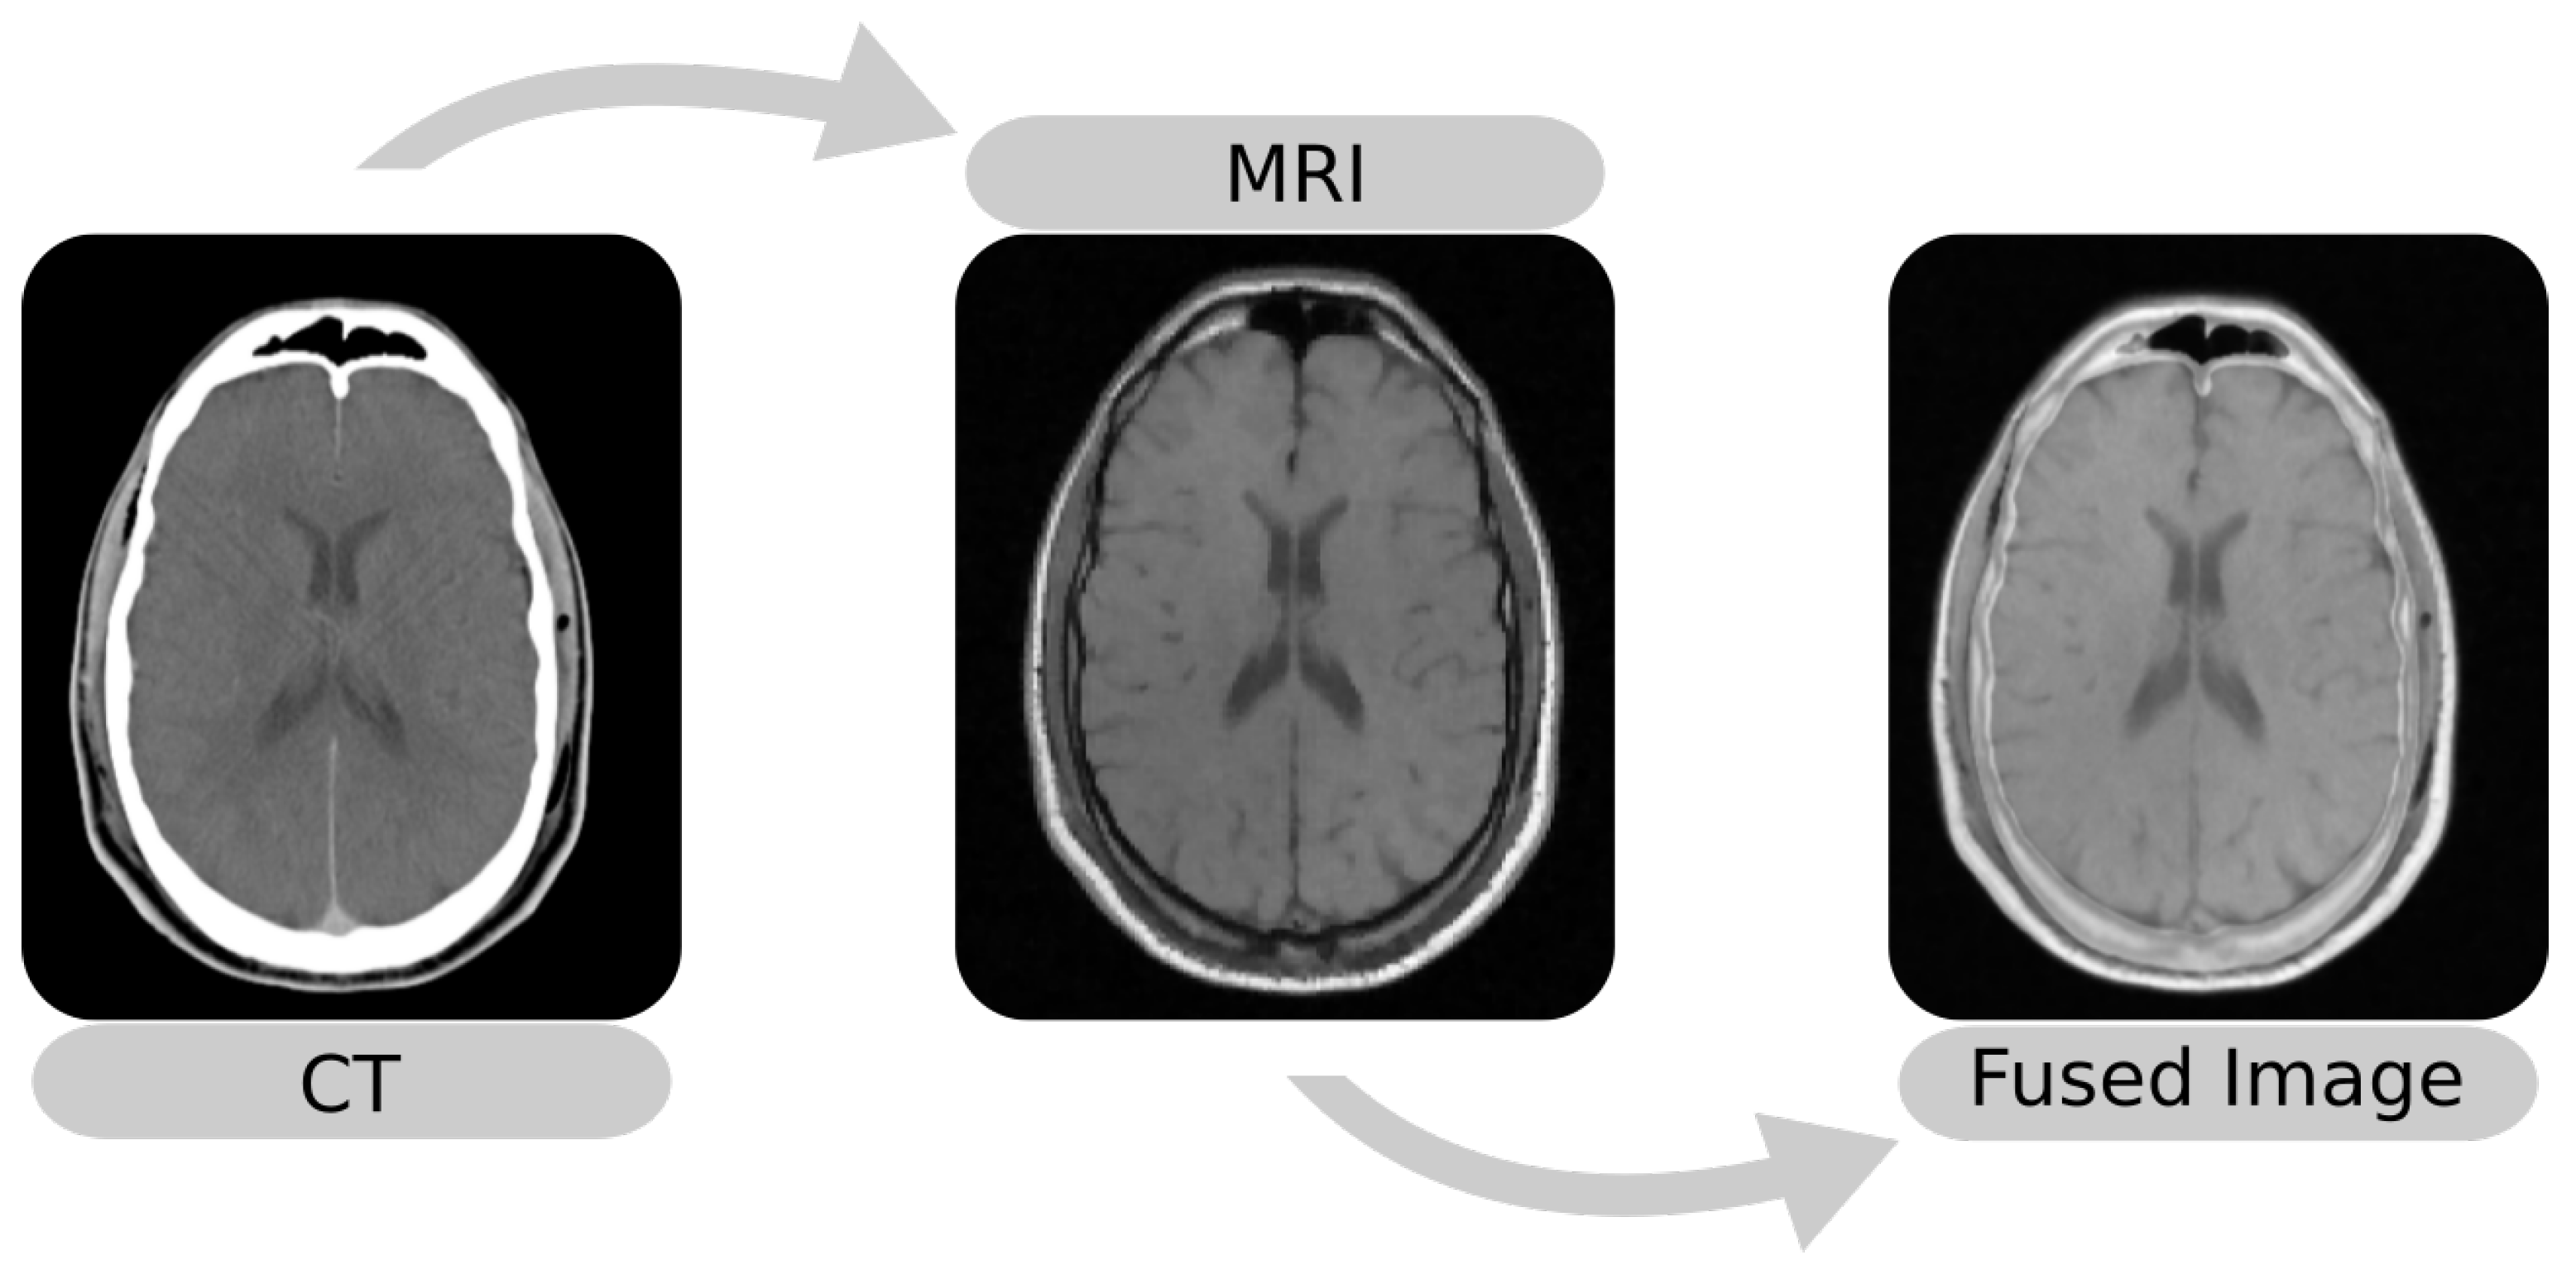

The image fusion (Figure 1) maps images into the same coordinate system and then blends the aligned result into an output image. Among the methods for image fusion, characteristics such as imaging modalities determine the performance of a procedure. For example, methods that use the Mean-Squared Difference (MSD) as the optimization metric perform better in single-modality fusion [10,11]. Thus, it is essential to know the performance of these techniques, especially in applications such as SEEG that involve external objects.

Figure 1.

Example of multi-modal image fusion between an MRI and a CT. The images were taken from Patient 001 of the RIRE dataset [12].